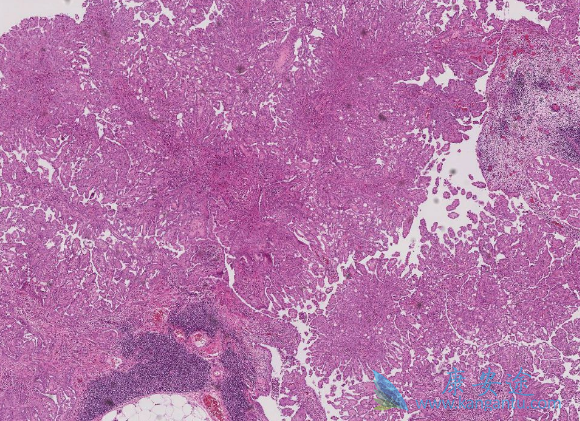

间皮瘤是一种罕见的恶性肿瘤,主要是由接触石棉引起。在美国,每年超过2000人被诊断为间皮瘤,而且确诊时大都为晚期。目前对于间皮瘤的治疗还没有标准疗法,医生只能根据每位患者的具体情况治疗治疗方法。虽然如此,此类患者的预后很差,一般术后中位生存期也大约在1年左右。也因此被称为恶性间皮瘤。

恶性间皮瘤有哪些症状?在早期,60%~90%的患者出现呼吸困难、胸痛、干咳和气短,约10.2%病人可以有发热及全身不舒服等症状,3.2%病人以关节痛为主诉症状。到了中晚期,50&-60%的患者表现为大量胸腔积液,其中血性胸腔积液占3/4。晚期患者表现为衰弱、恶病质、腹腔积液以及胸腹部畸形。临床表现是肿瘤进行性侵袭而未受到有效控制的结果。